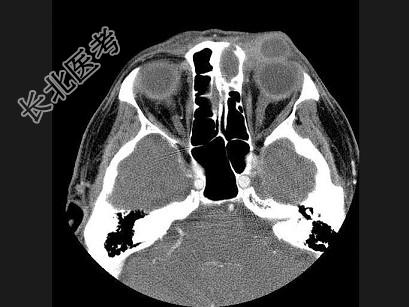

- 单项选择题女,40岁, 眼眶周围软组织发红、肿胀3周,CT扫描如图, 最可能的诊断是 ( )

A、左侧眼眶黏液瘤

B、左侧眼眶脓肿

C、左侧眼眶黏液囊肿并感染

D、左侧眼眶脂肪瘤

E、左侧眼眶血管瘤